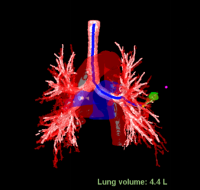

王大伯术前CT

原来,陈恩国主任医师团队运用了最新的BTPNA技术,简单来讲,就是在原有的导航技术上升级了一个经支气管向病灶方向打隧道的办法。 这样,很多原来没有支气管相联通的肺结节,常规导航技术难以到达,现在也可以通过这个技术轻易到达啦! 虽说就是打一条通往结节的隧道,但其中技术含量可没那么简单。要保证安全和准确,术前精密的计算和路径设计非常重要。 王大伯术前,陈主任呼吸内镜介入团队利用最新一代的虚拟导航Lung pro系统对王大伯的胸部CT进行了三维重建,计算出最佳经支气管镜到达病灶的路径,并对手术路径的可行性进行讨论,对可能出现的各种情况进行分析。

术前规划/评估:病灶位置及最佳气道内路径